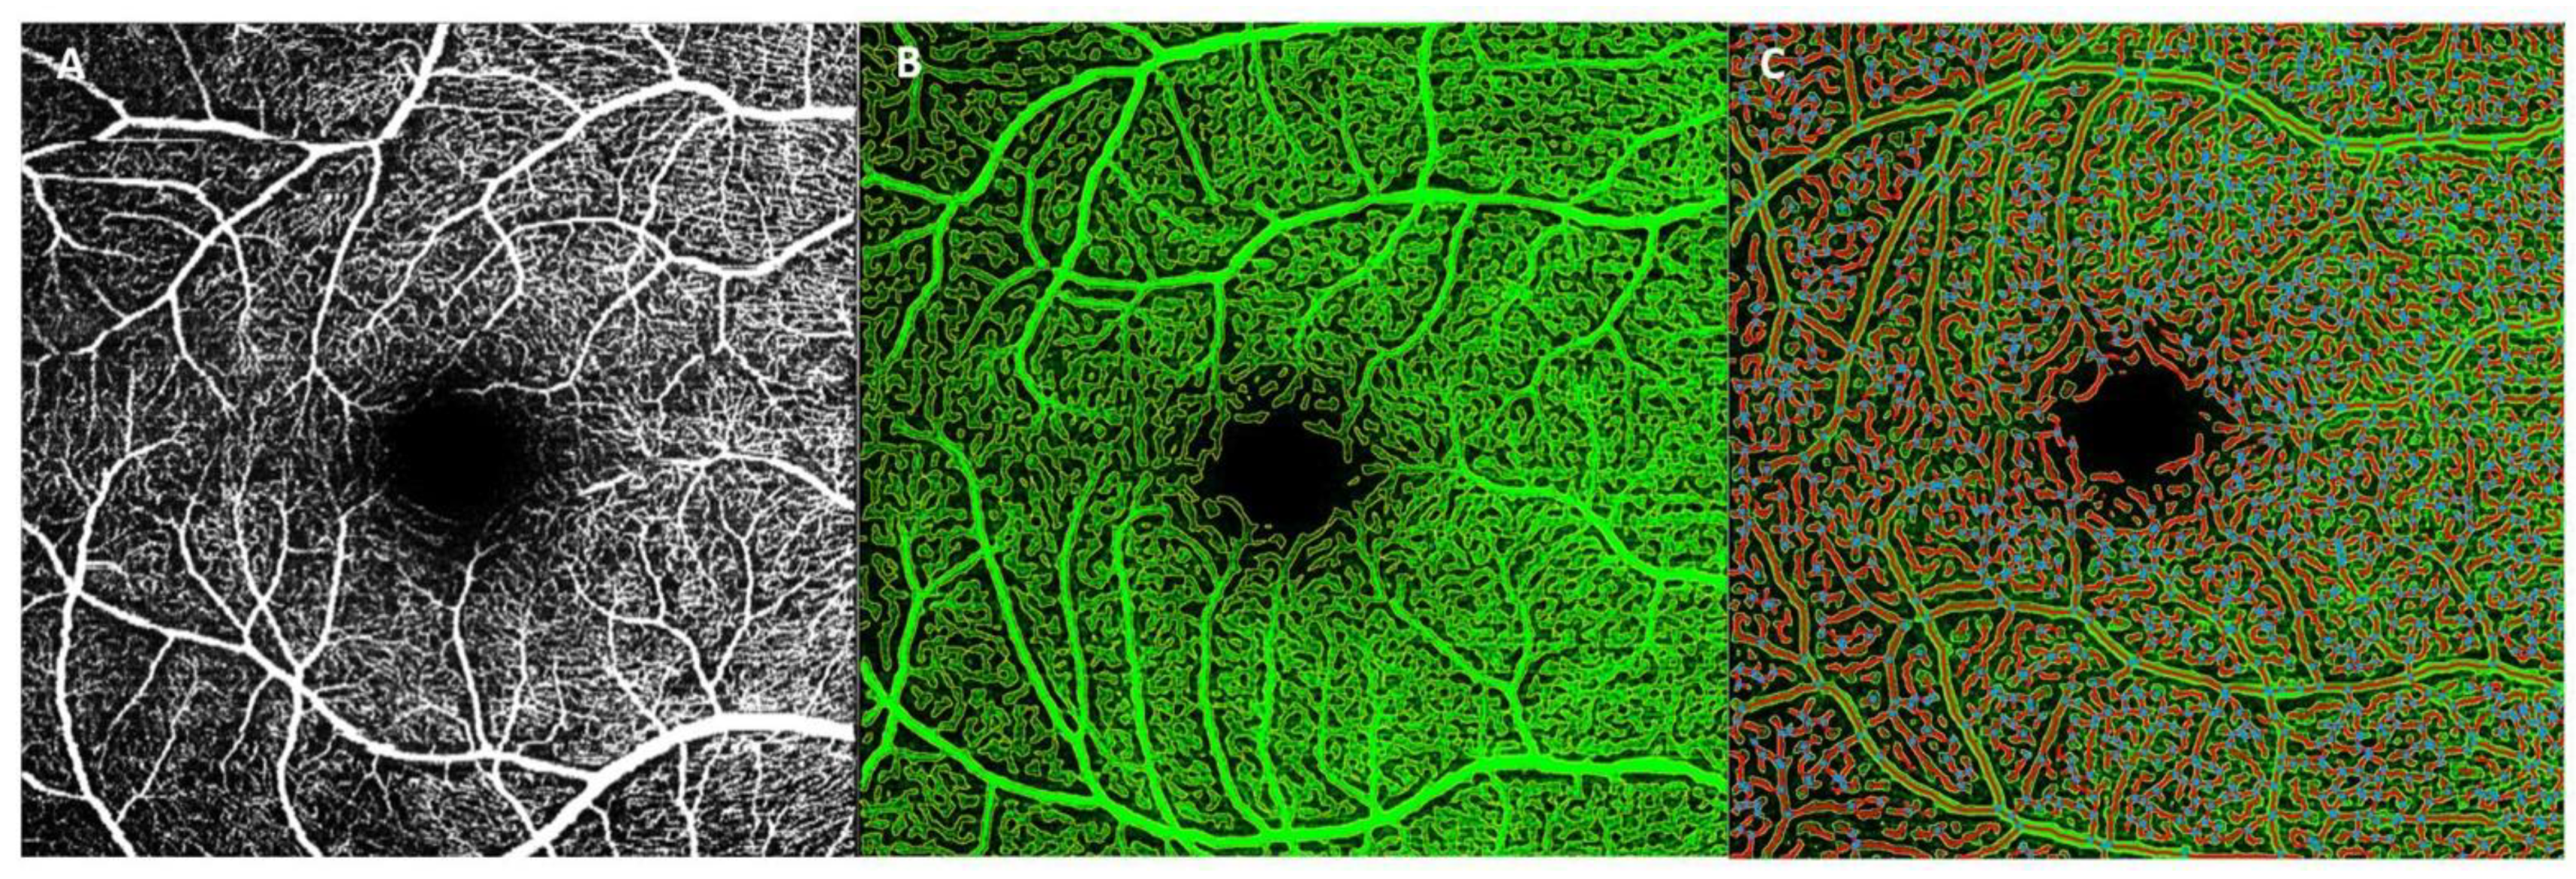

2.4.1. AngioTool

2.4.2. Erlangen-AngioTool

2.7. Colorimetric Scale